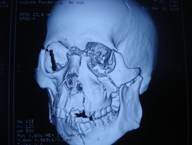

A cook by profession, Mr. Ata-Urrehman, sustained severe multiple skull fractures crumbling the face drastically and critical injuries aggravating the situation further. There were fractures on lower jaw (Mandible), nose, forehead, Zygoma, cheek-bones (Maxilla), and orbital bones with leakage of brain fluid (Cerebrospinal fluid) which made Mr. Ata-Urrehman’s case extremely complicated. He received a primary treatment at a private hospital in Barabanki from where he was referred to a reputed Hospital in Lucknow. The doctors, in the said Hospital, after acknowledging the severity of the injury and the deterioration in his condition, referred the patient to some other higher medical centre.

As a last ray of hope, Mr. Ata-Urrehman was rushed to Sahara Hospital. The Trauma Care Unit of Sahara Hospital, immediately assigned the case to a team of seasoned Plastic Surgeons, who after screening the complications involved in the case, decided to proceed with the surgery without any further delay. The patient underwent a two-staged surgery. In stage-1, debridement and fixation of the lower jaw (Mandible) was done. In stage-2, reshaping of the forehead, nose, cheek-bones (Maxilla) and Zygoma was done by approaching through the scalp area. The duration of the stage 1 surgery was 4 hours while that of the stage-2 surgery was 6 hours.

CT Scan |